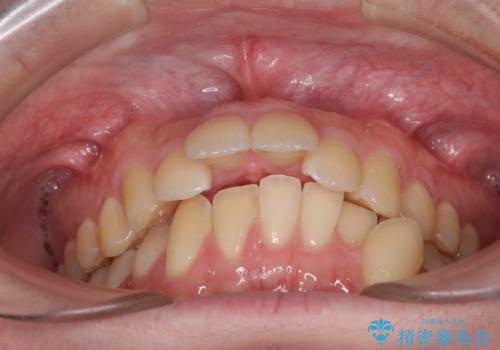

- 上顎の前突感による口の閉じにくさと八重歯を気にして来院された患者様です。

目立たない装置を希望されたので、上顎が裏側装置のハーフリンガルを選択し、上下左右の小臼歯(計4歯)を抜歯して矯正治療を行うこととしました。

下顎骨が左側に大きく変位しているため、上下の正中位置は極力一致するところをゴールとしました。

上下顎で左右差の大きい抜歯矯正を裏側装置で行ったため、非常に時間がかかりましたが、正中位置も良い位置に改善され、気になっていた突出感も解消されました。